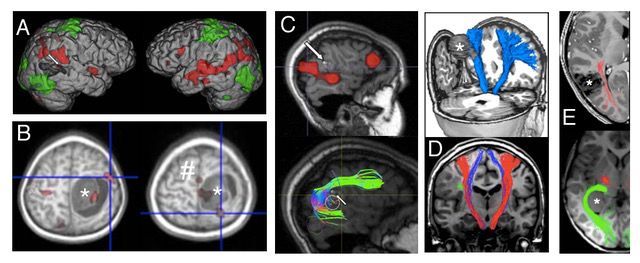

Sorgfältige und individualisierte Planung der Operation auf der Basis hochwertiger MRT Bildgebung, die je nach Lokalisation des Befundes ergänzt werden sollte durch die Darstellung von Motorik und Sprache, Darstellung relevanter Faserbahnsysteme, Charakterisierung des Stoffwechsels, Darstellung von Blutgefäßen und Hirnnerven. Vieles davon können wir dank einer spezialisierten Forschergruppe in Kinderklinik und Neuroradiologie häufig bereits für relativ kleine Kinder realisieren.

Die sogenannte „Zugangsplanung“ sollte die bestmögliche Darstellung des Tumors bei gleichzeitiger Minimierung von Schäden durch den Weg zum Tumor ermöglichen.